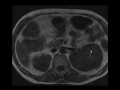

Erdheim Chester Disease

Patient with abdominal pain. MR images demonstrate a T2 hypointense rind of soft tissue surrounding both kidneys, and a nuclear medicine bone scan demonstrates intense radiotracer uptake in both lower extremities, a constellation of features associated with Erdheim-chester.